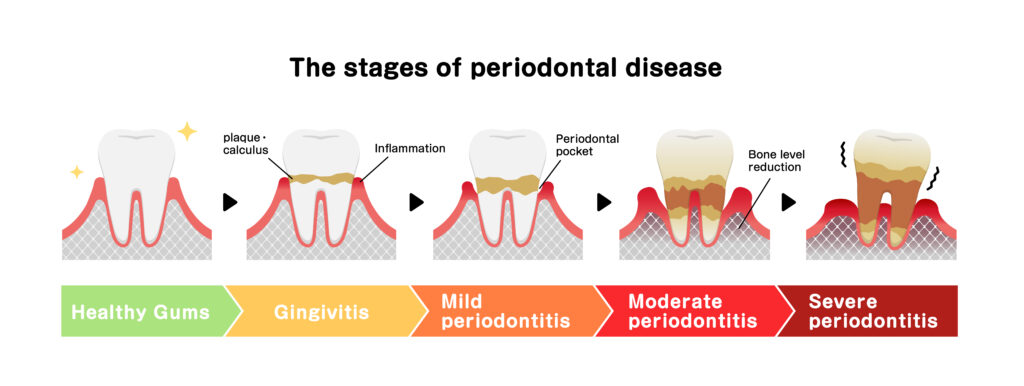

Gingivitis is the early stage of gum disease. It begins when plaque is left along the gumline and irritates the gum tissue. At this point, the gums may look red, swollen, or may bleed easily, especially when you brush your teeth or floss. Gingivitis affects the surface level of the gums and does not involve bone loss. The good news is that gingivitis can often be fully reversed with good oral hygiene and a professional cleaning that removes tartar and bacteria.

Periodontitis is a more serious form of periodontal disease. Instead of affecting only the surface tissues, periodontitis begins to damage the ligaments and bone that support the teeth. As the infection progresses, deep pockets can form around the teeth, and the gums may start to pull away, leading to gum recession. Left untreated, this stage of gum disease can lead to mobility issues and even tooth loss. Periodontitis cannot be reversed, but it can be controlled with the right periodontitis treatment and consistent follow-up care.

The main difference between gingivitis and periodontitis is how deeply the inflammation has spread. Gingivitis affects only the gums. Periodontitis involves the gums, the ligaments, and the bone that hold the teeth in place. Once the bone is affected, this becomes a more advanced condition.

Gingivitis is usually reversible with improved home care and a dental cleaning that removes tartar and plaque. Periodontitis causes permanent structural changes because bone does not grow back once it has been lost. We can treat and manage periodontitis, but we cannot undo the bone damage that has already occurred.

Untreated gingivitis can eventually advance into periodontitis, especially if plaque and tartar remain along the gums. Over time, the body responds to the bacteria by breaking down surrounding tissues. When that happens, the condition moves from an early-stage problem into an advanced gum disease that requires deeper treatment.